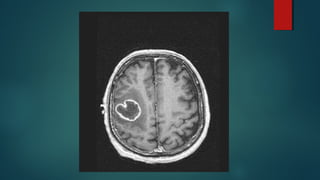

Este documento es el programa para un taller de imágenes del curso de emergencia 2015 impartido por el Dr. Víctor Delgado. El taller se centra en el uso de imágenes médicas para el diagnóstico y tratamiento de pacientes en coma traumático según la base de datos de Marshall. El Dr. Delgado es el único instructor repetido a lo largo del documento.